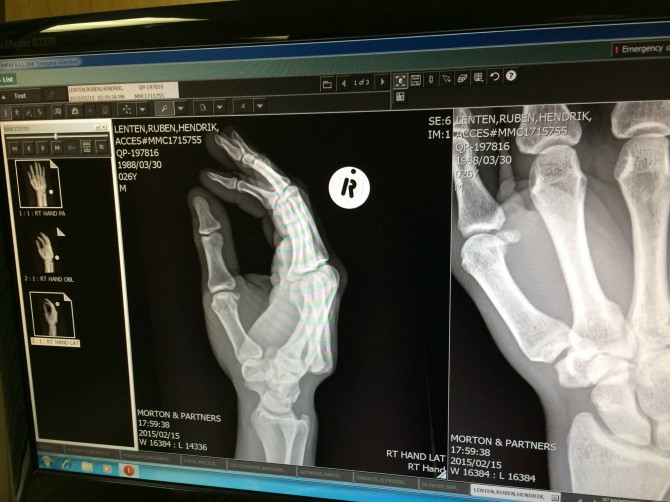

The X-Ray – Photo: Ruben Lenten

Getting back on the board and getting into the groove by rocking a nice Boogie Loop. Followed by a my signature Skycatcher handlepass, which I mistimed and crashed really really hard… broke my board in half and felt my body was pretty beat. Feeling all the frustration of seeing my dream vanish in minutes I hit the sand and hurt myself even more… luckily only dislocated my hand!

The outcome… Heal up soon Ruben!